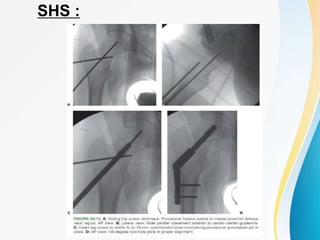

SLIDING HIP SCREW SHS :

SHS :

TIP APEX DISTANCE : TAD

• Sum of distances from the tip of the lag screw

to the apex of the femoral head on both the

anteroposterior and lateral radiographic views.

• The sum should be <25mm to minimize the risk

of lag screw cutout .

• TAD > 25 mm , the surgeon should reassess

the fracture reduction and position of Guide

Pin.